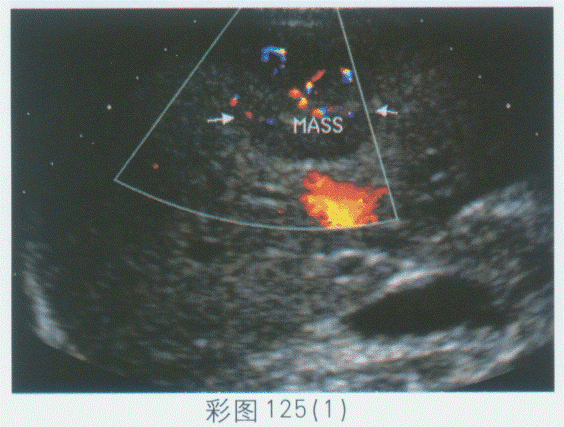

临床资料:男,57岁,自述患乙肝、肝硬化十余年。临床化验检查:CEA、AFP均升高。超声综合描述:彩图125(1):肝表面不平,实质回声粗糙不均,肝右叶可见3.1cm×3.2cm圆形低回声区,边界清晰,内回声欠均,CDFI:内见较丰富血流信号,为动脉波形,门静脉1.4cm,为入肝血流,血流通畅。彩图125(2):射频消融治疗后3天,肝右叶由低回声区一回声增强,周边缩瘪样改变,CDFI:内未见血流信号,周边可见散在点状血流信号。

A.彩图125(1)原发性肝癌;彩图125(2)射频消融后肿瘤血管灭活

B.彩图125(1)原发性肝癌;彩图125(2)射频消融后肿瘤周边血管灭活不彻底

C.彩图125(1)原发性肝癌;彩图125(2)射频消融后肿瘤内血管灭活不彻底

D.彩图125(1)原发性肝癌;彩图125(2)射频消融后肿瘤血管未灭活

[单选题]临床资料:男,57岁,自述患乙肝、肝硬化十余年。临床化验检查:CEA、AFP均升高。超声综合描述:彩图125(1):肝表面不平,实质回声粗糙不均,肝右叶可见3.1cm×3.2cm圆形低回声区,边界清晰,内回声欠均,CDFI:内见较丰富血流信号,为动脉波形,门静脉1.4cm,为入肝血流,血流通畅。彩图125(2):射频消融治疗后3天,肝右叶由低回声区一回声增强,周边缩瘪样改变,CDFI:内未见血流信号,周边可见散在点状血流信号。超声提示()A . 彩图125(1)原发性肝癌;彩图125